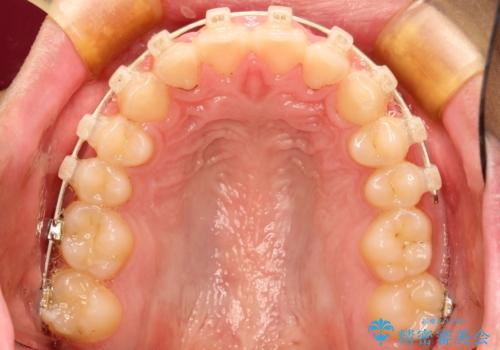

初診時の歯並びの状態としては、上下ともに前歯部の中等度のがたつきがあり、前歯には正中離開があり過蓋咬合を呈してい状態でした。

また奥歯の噛み合わせのズレもあり、特に左は顕著に認められました。

検査の結果、抜歯なし/ワイヤー矯正にて治療を行いました。

また、成長期終盤の男の子だったため成長の余力(下顎を前に牽引んし成長を促進する)を期待しアドバンシンクという装置を使い、下顎の骨の成長を利用した矯正治療を行いました。